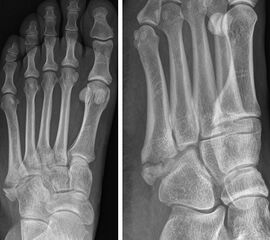

In der Literatur herrscht weitestgehend Einigkeit darüber, dass Lawrence und Botte Zone I Frakturen (Abb. 3) konservativ behandelt werden können 151617. Allerdings variieren die beschriebenen konservativen Behandlungskonzepte stark. Empfohlen werden die elastischen Wickelung bis zur Immobilisation im Unterschenkelgips/-walker, sowie die schmerzabhängige Vollbelastung bis zur vollständigen Entlastung 18. Häufig werden eine Dislokation von mehr als 2 mm, oder die intraartikuläre Fraktur (>30% der Cuboid-Metatarsalen Gelenkfläche) als Operationsindikation angesehen. Allerdings ist den Autoren keine prospektive Studie bekannt, welche ein konservatives gegen ein operatives Therapieregime verglichen hat. Egol et al. 15 publizierten eine prospektive Studie zur frühfunktionellen Nachbehandlung (schmerzabhängige Vollbelastung und festes Schuhwerk) von 49 Patienten mit einer Lawrence und Botte Zone I Fraktur (50% Intraartikulär, 32% > 2mm Dislokation). 94% der Patienten konnten nach 6 Wochen den Fuß voll belasten. Die mittlere Zeit der Arbeitsunfähigkeit betrug 22 Tage. Die volle Sportfähigkeit war bei 86% der Patienten nach 6 Monaten, bei allen Patienten nach einem Jahr erreicht. Weder der Grad der Dislokation noch die intraartikuläre Beteiligung hatten einen signifikanten Einfluss auf diese Zielparameter.

Lawrence und Botte Zone II

Abbildung 4